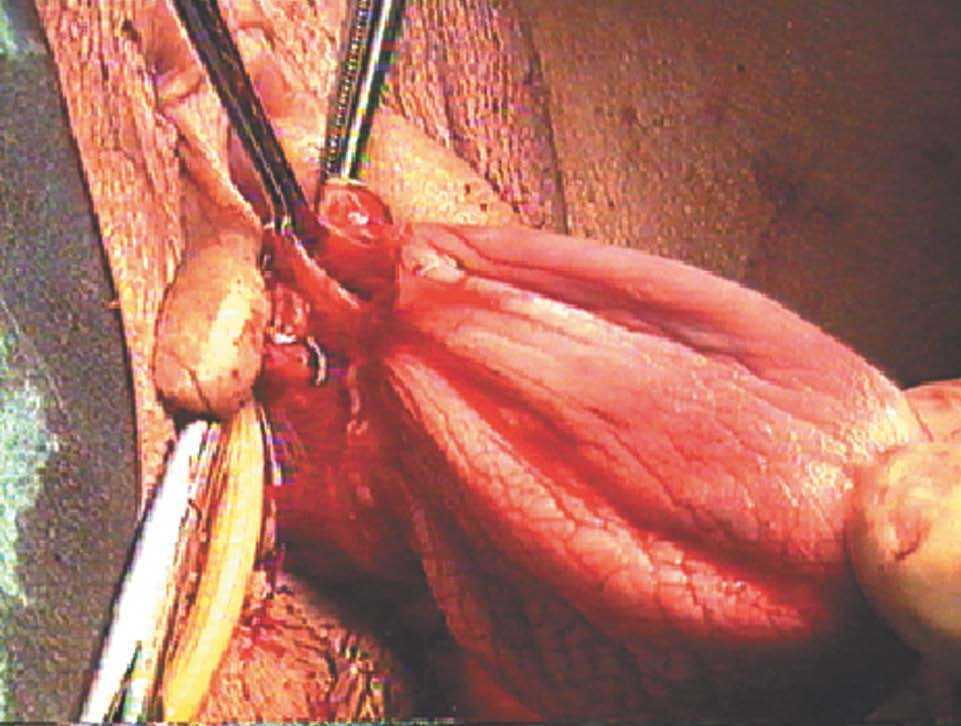

-- Paso primero. Disección del peritoneo presacro hasta el fórnix vaginal por su vertiente derecha (fig. 8).

Figura 8.Detalle del peritoneo presacro.

-- Paso segundo. Disección de la cúpula vaginal (fig. 9).

Figura 9.Detalle de la cúpula vaginal.

-- Paso tercero. Disección del espacio vesicovaginal y del espacio rectovaginal hasta el músculo pubococcígeo (figs. 10-13).

Figuras 10 y 11.Detalle de la disección vesicovaginal.

Figuras 12 y 13.Detalle de la disección del espacio rectovaginal.